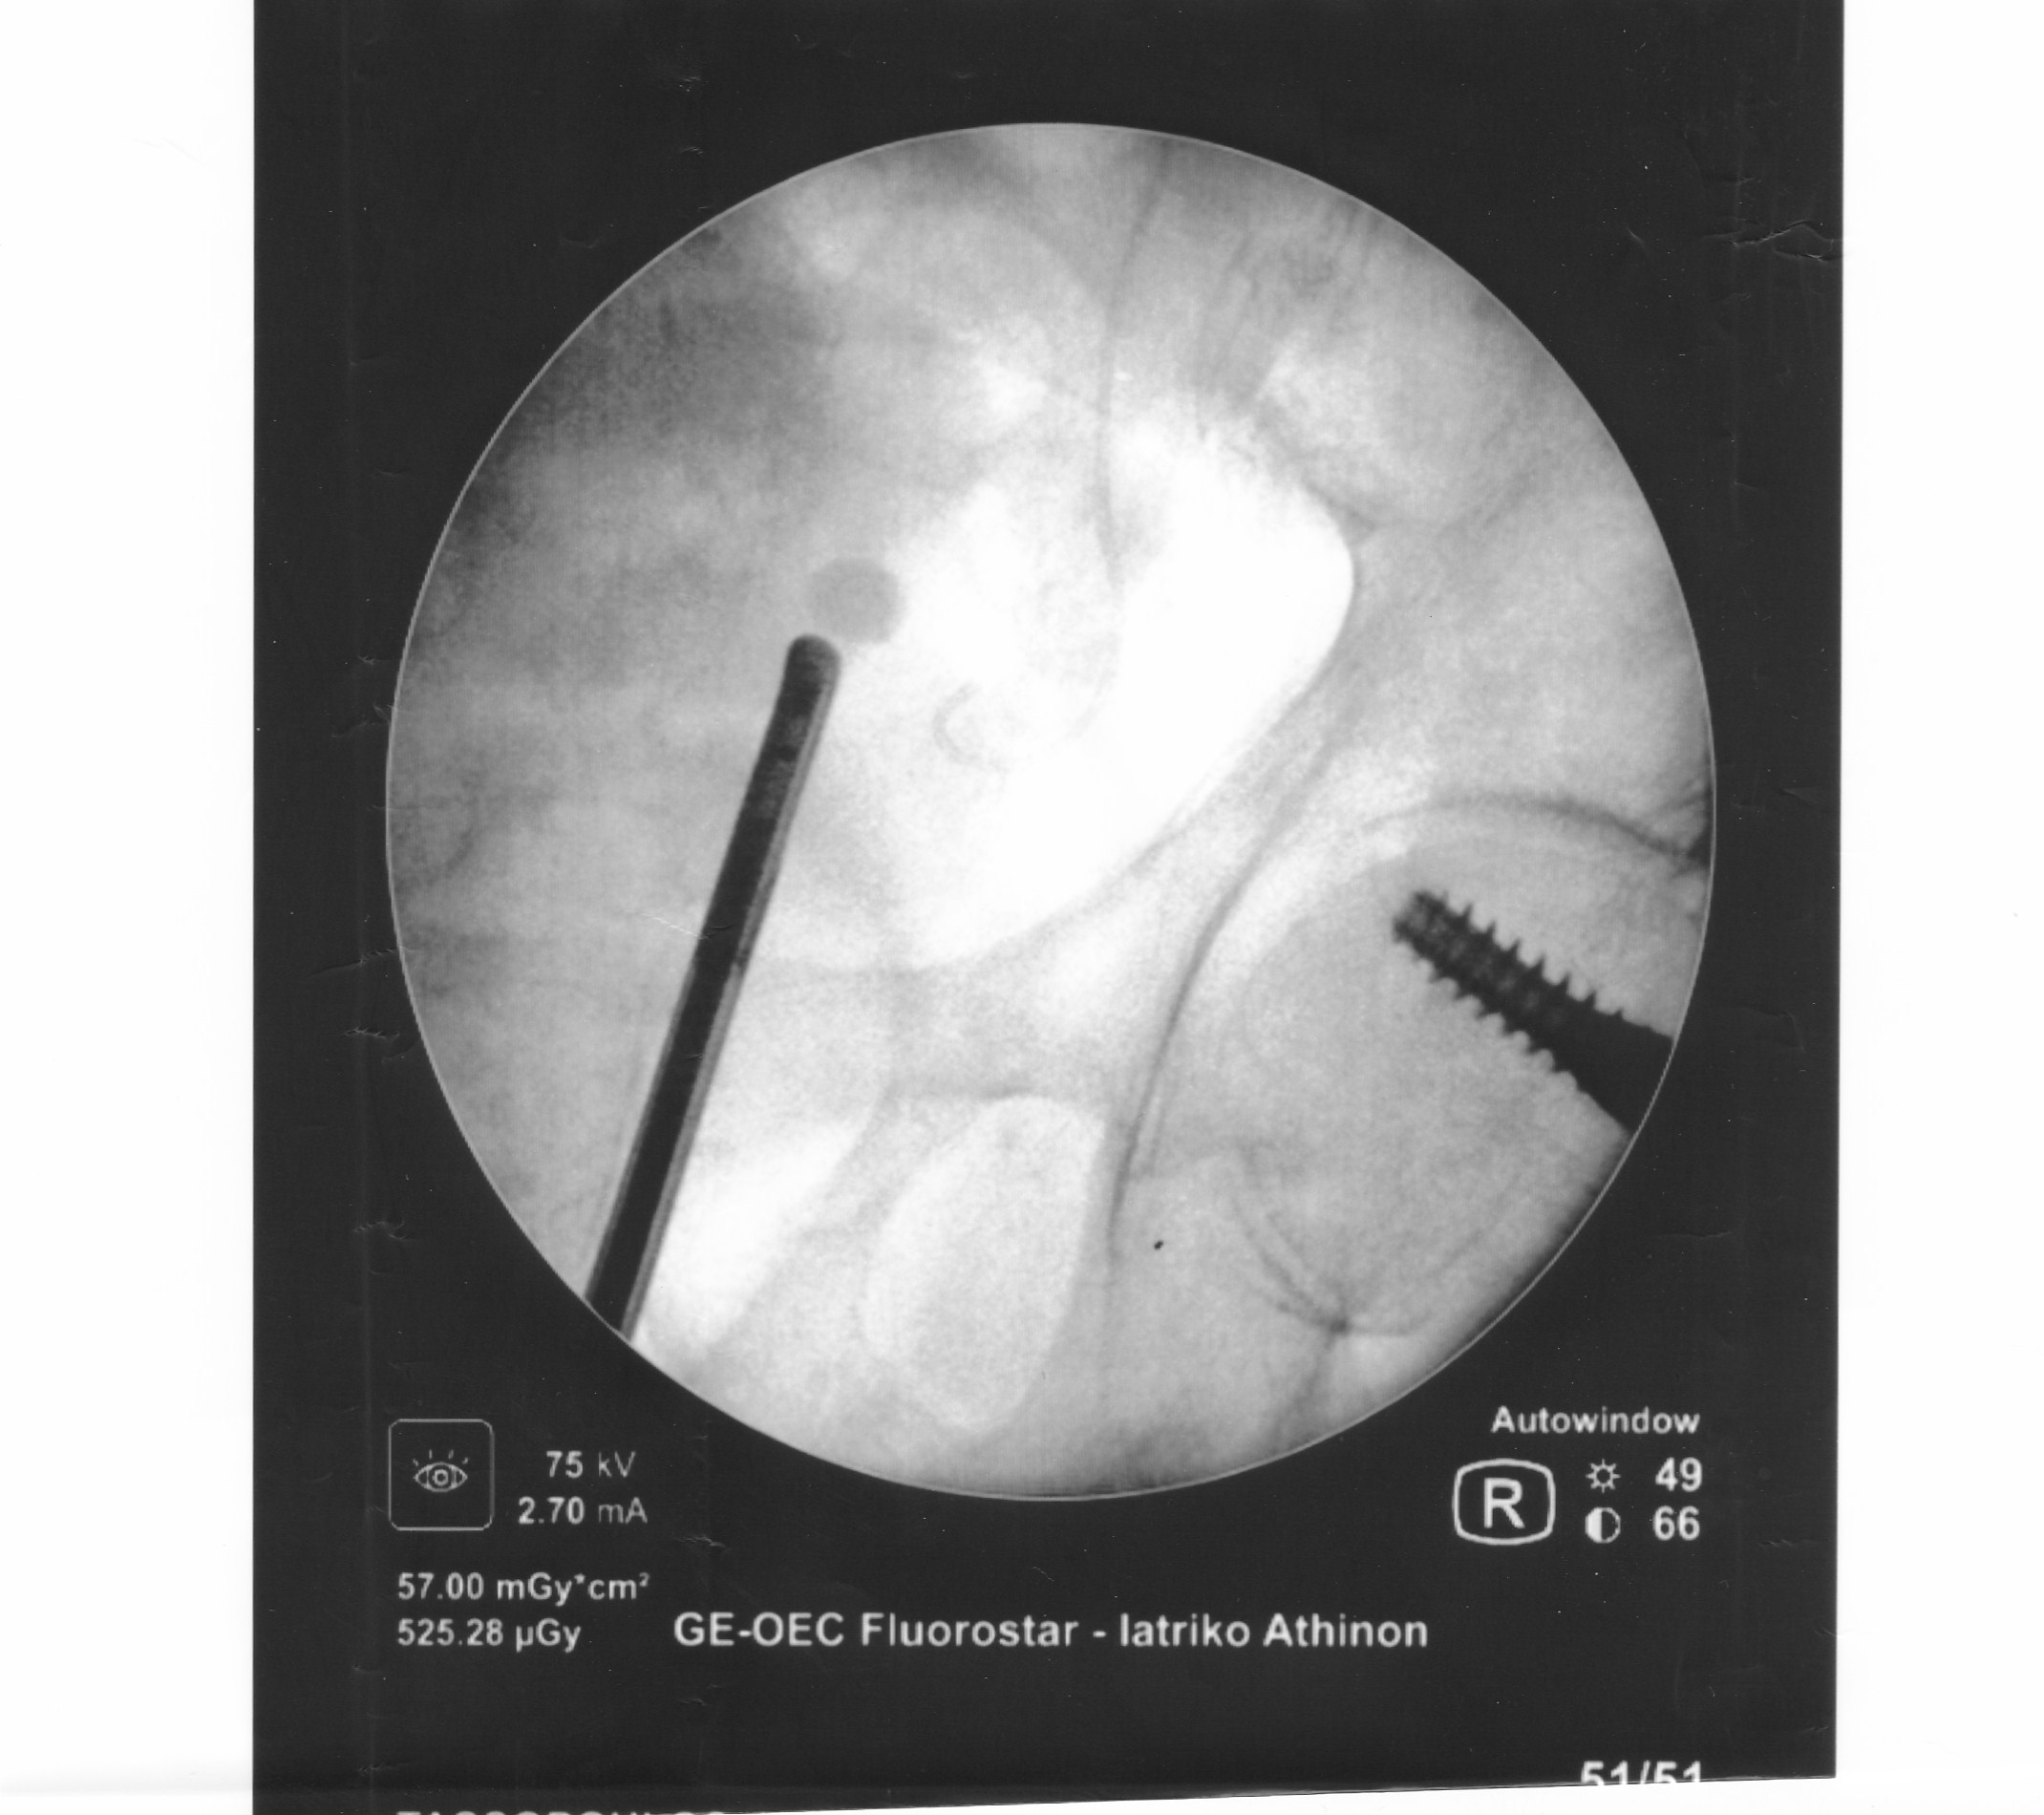

Είναι γνωστό ότι η Λιθίαση (πέτρες) της ουροδόχου κύστεως (σχήμα 1) θα πρέπει να αντιμετωπίζεται με σύγχρονες Ενδοσκοπικές τεχνικές.

Ενδοσκοπική Holmium Laser Κυστεολιθοτριψία